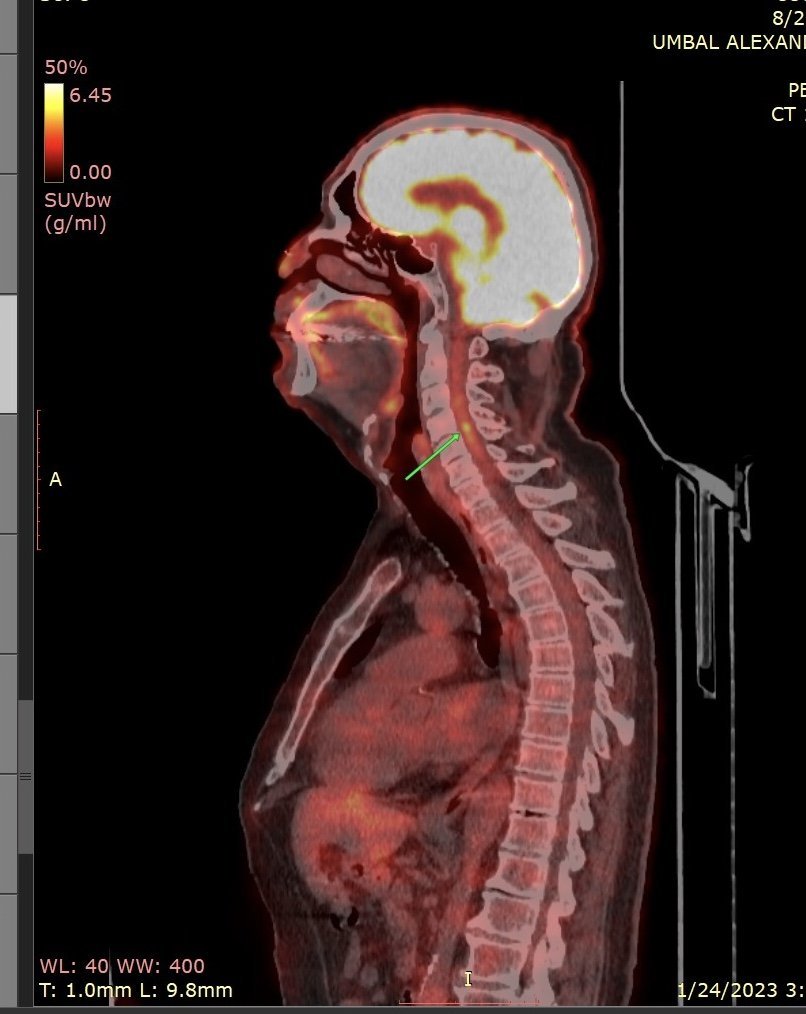

Благодаря за бързите и подробни отговори! Утре ще звъня поред за ЯМР, дано успея! И не - в разчитането от Александровска (споделяла съм го и тук) нито буква за тази находка! Георгиев от Сити уж гледа подробно, особено гръбнака - каза, че не вижда причина болката да е с генеза от там. Прилагам снимката, която д-р Недев ми прати (евала на такива доктори - в неделя, без да има комерсиалност).

Да, това трябва да се огледа на ЯМР с контраст. Странна точка с умерено завишен SUV (5-6). Обаче и разположението - в центъра на канала - за мен също е леко озадъчаващо.